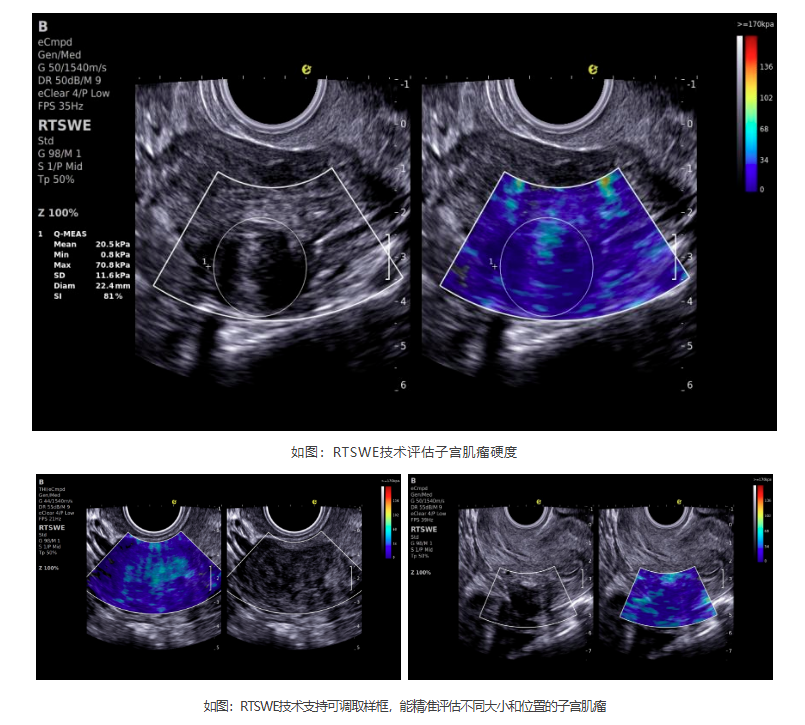

如今,新航娱乐医疗ePascal东风系列搭载的RTSWE?实时E成像技术为肌瘤良恶性的鉴别带来了突破!该技术基于OmniSound? 平面波超快速平台,以25000帧/秒的采集帧频,实现最小0.4mm病灶的精准硬度测量。它犹如为超声检查赋予"智能触诊"能力,通过定量分析组织硬度,辅助判断肌瘤性质:

良性肌瘤:质地均匀,硬度较高(类似橡皮)

恶性肉瘤:硬度不均,整体更坚硬(类似石头)

变性肌瘤:如红色变性时,硬度会相应降低

RTSWE?技术优势

? 安全无创——零辐射、无痛苦,检查更舒适

? 减少过度检查——降低不必要活检

? 生育友好——专为备孕女性定制肌瘤评估方案

? 动态监测风险——敏感捕捉绝经后肌瘤的异常

? 指导精准治疗——为手术决策提供客观依据

cd2301cd65513af0501835669682402.png

潜伏在子宫里的"小石头",看似无害,却需要及时关注。新航娱乐医疗RTSWE?实时E成像技术以毫米级精度实现子宫肌瘤可视化诊断,突破性探测病灶质地特性,为临床决策提供新维度。该技术助力女性通过精准超声检测,获得更安心的健康保障。